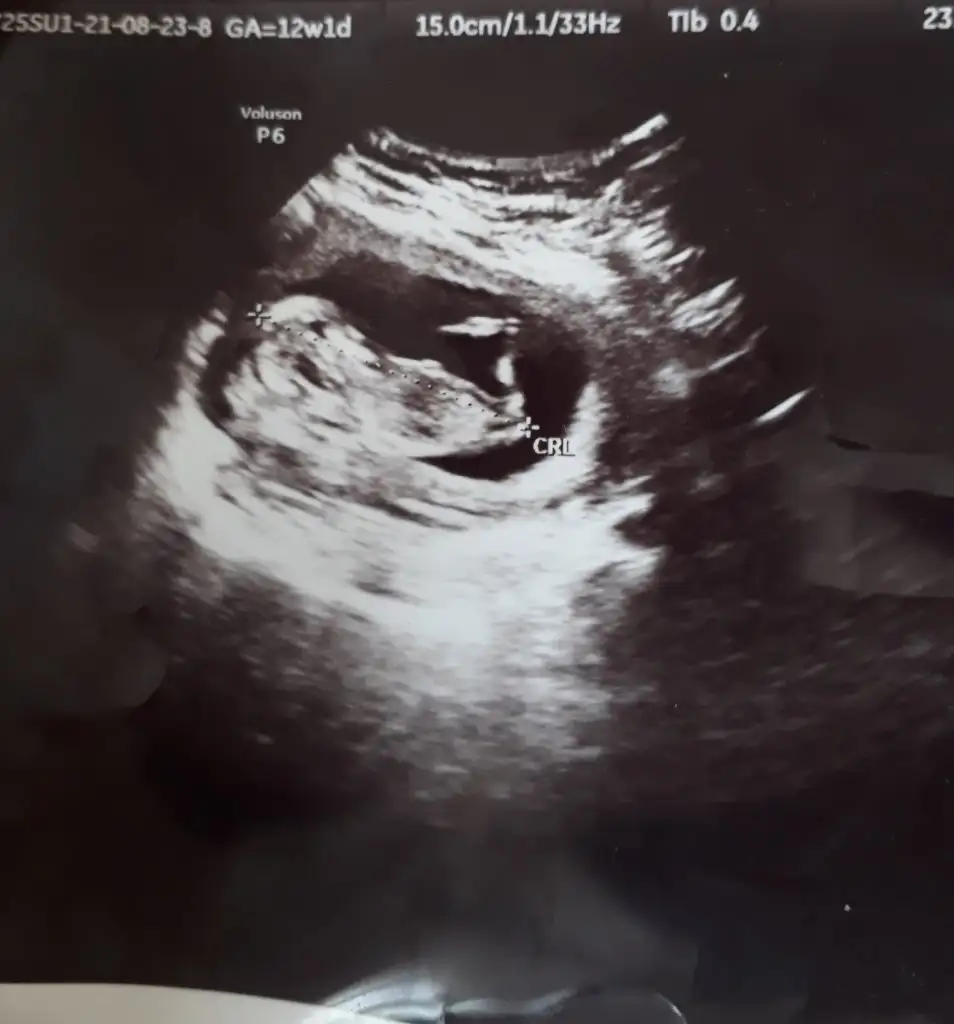

Erkek ve kız için 11 + 12+ yada 13 hafta usg görüntüsü olmalı açıklamalar asagıda yazıyor 😊 rabbim herkesin gönlüne göre nasip etsin inşallah .. ecmain

[/B]Eki Görüntüle 473828 gordugunuz gibi ust taraftaki simgedende anlasildigi gibi eger cikinti paralel ise kiz

yok 30°lik bir aciyla yukari dogru bakiyorsa %99 oglunuz olacak demektir simdi bi kac ornek resimler daha koyacagim kiziminkide dahil

Eki Görüntüle 473829 bu bir erkek bebek genital nub cikintisi gayet yukarda

Eki Görüntüle 473831 simdi burada cikintilara bakin eger bel popo cizgisine paralel ise kiz

yok 30 derecelik bir aciyla yukari bakiyorsa erkek

yabancilarin hepsi biliyor bunu biz neden eksik kalalim gayet bilimsel simdi ellerinde11 12 13 ultrason fotografi olanlar alsin hemen baksin yada koyalim buraya yorumlayalim